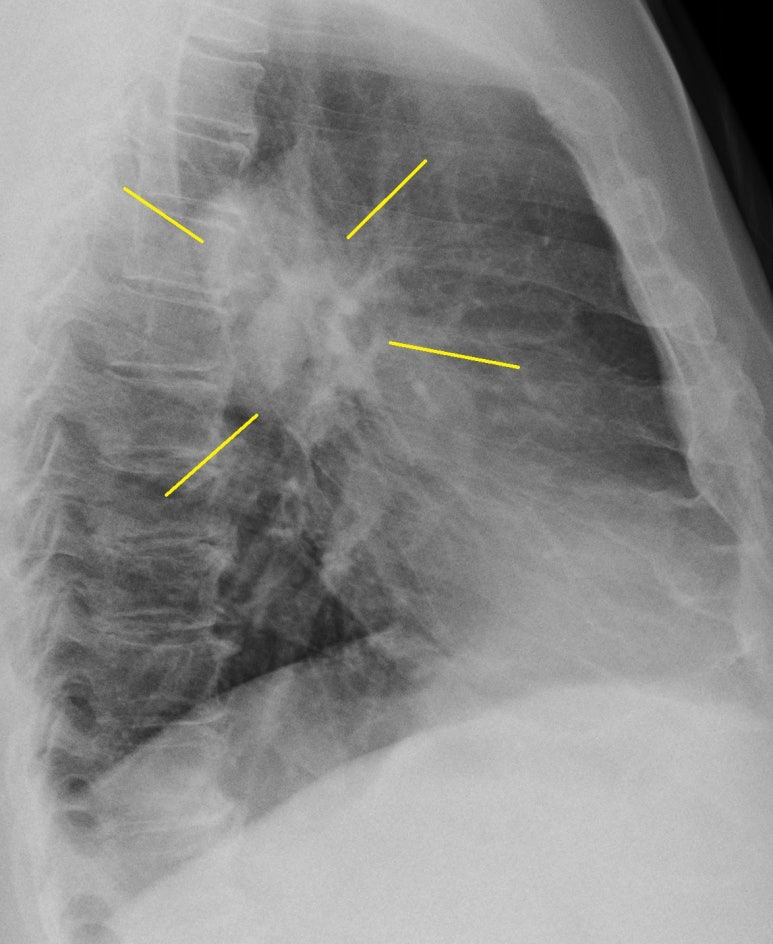

검진용 흉부촬영 1매를 시행하고, 아래 모습을 보자마자

검진은 중지

측면사진 추가로 촬영하고 폐렴에 대한 평가 및 투약 시작함

백혈구, 호중구 분획 증가

반응성으로 혈소판도 증가

crp는 정상의 29배 증가된 상태의 확인